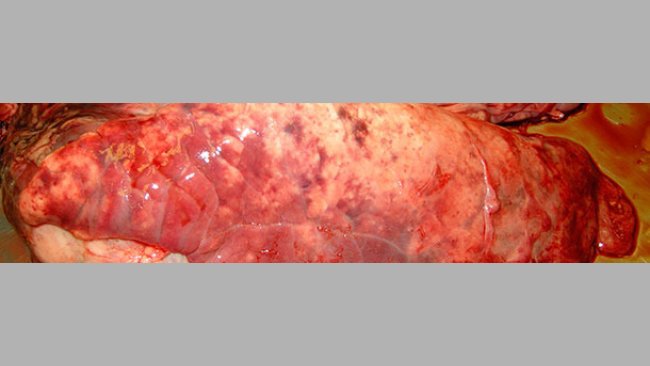

Cas clinique: Problèmes respiratoires et de reproduction dans un élevage de porcs

Après l’évaluation clinique et sérologique, on décide de vacciner contre le SDRP, ce qui permet une amélioration sanitaire de l’élevage. Quelques mois après une toux sévère apparait en engraissement puis en post-sevrage et aussi chez les truies.